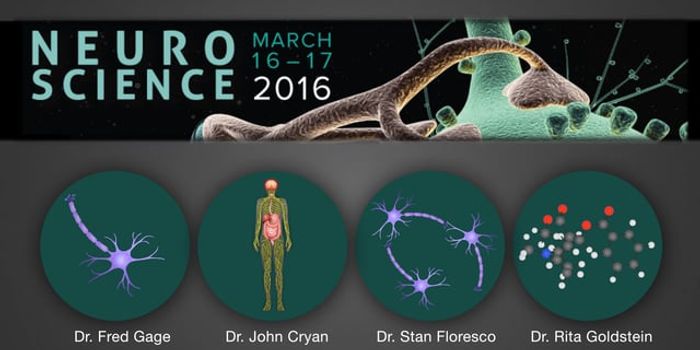

JAN 15, 2018VideosWhat makes us happy? Friends and family, of course, good times and being able to do what we love. But is neuroscience in ...